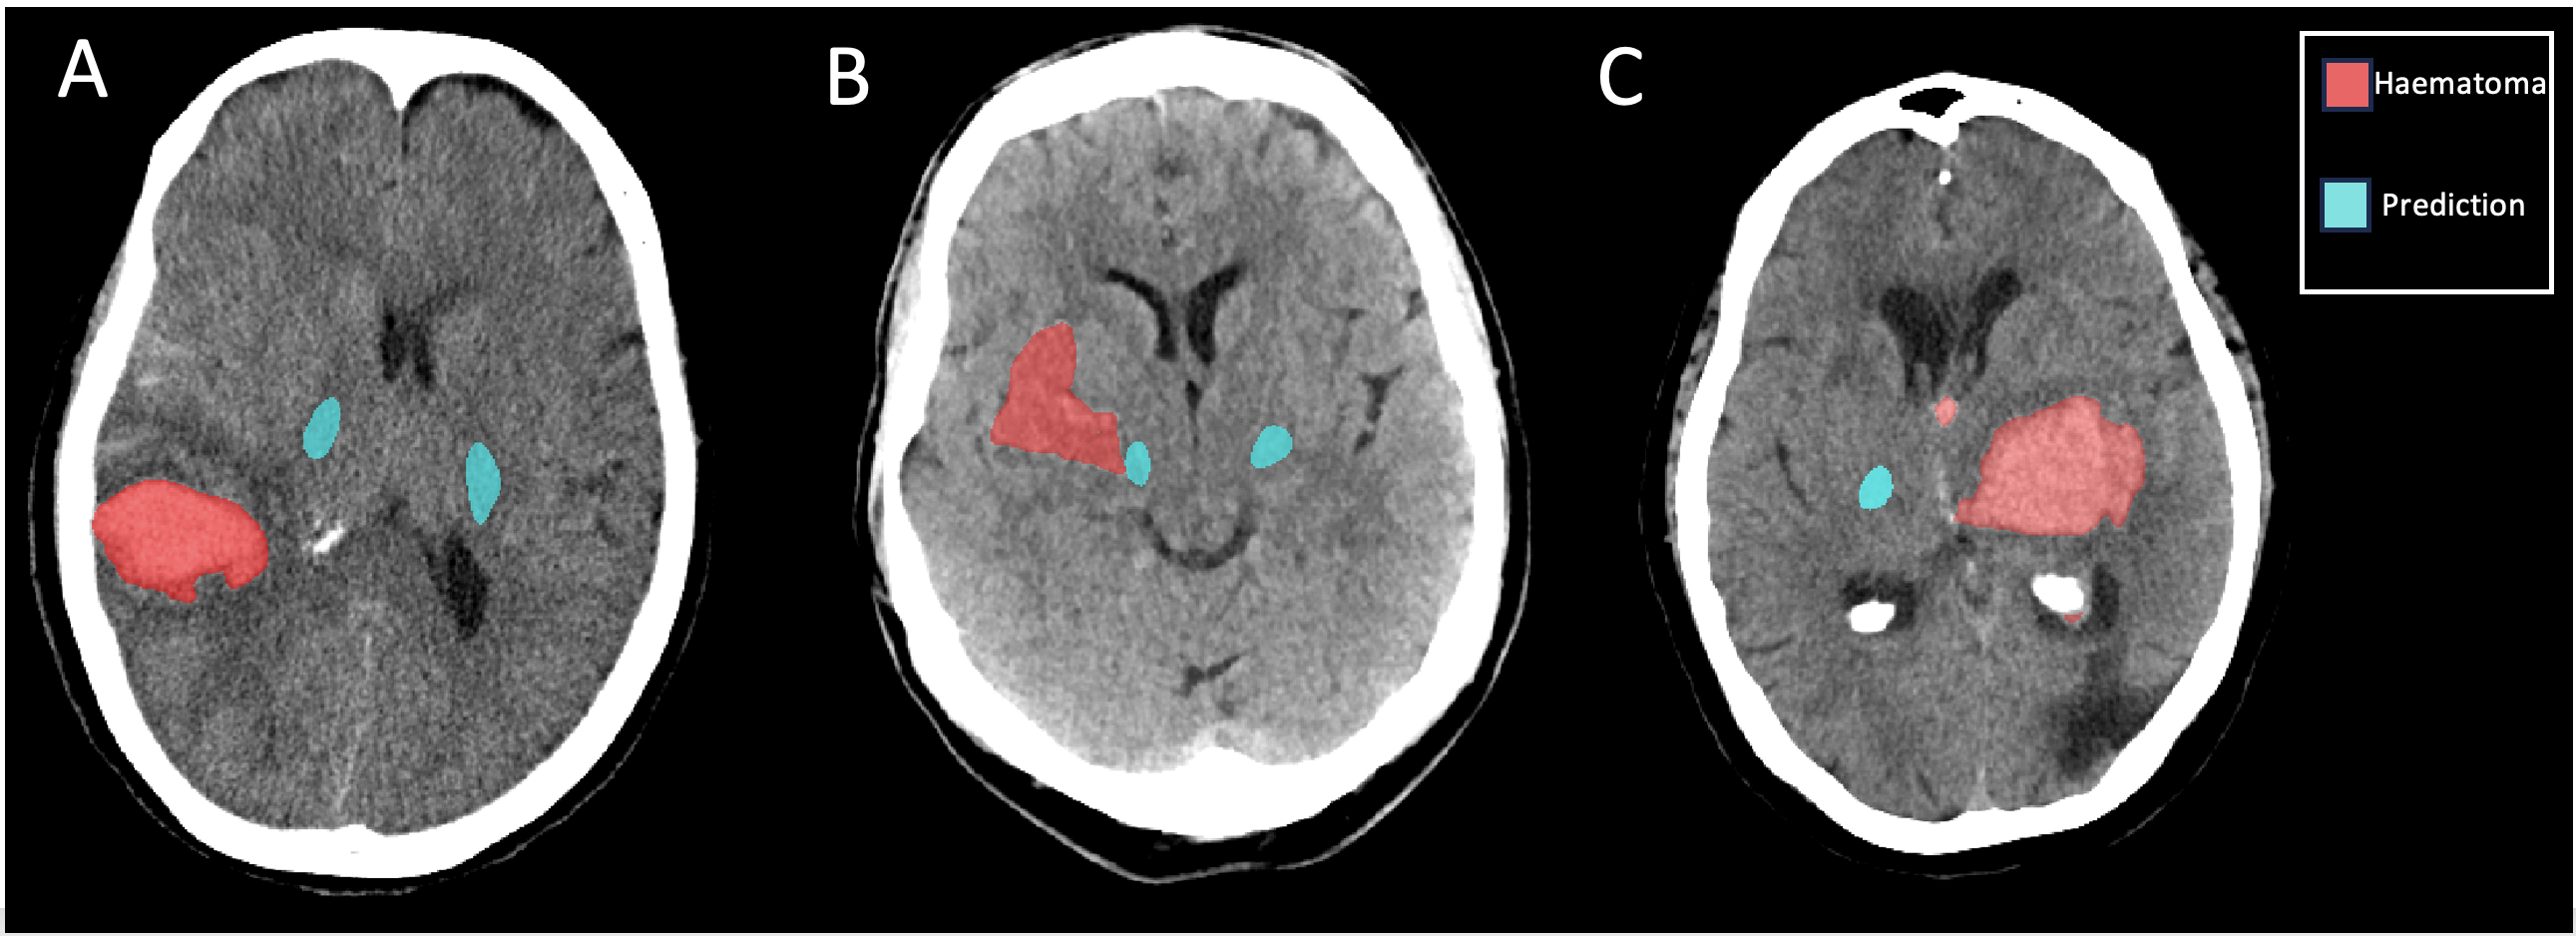

The mean DSC between the ground truth tractography segmentations in the testing dataset and the CST model’s predictions was 57%. Comparisons between the ground truth and model predictions for three patients can be seen in Figure 2. The mean DSC between the ground truth haematoma segmentations in the testing dataset and the haematoma model’s predictions was 94%.

Refer to caption

Figure 2: Three test cases for the CST segmentation model. The ground truth DTI CST tractography is shown in purple, the model prediction is shown in cyan. A) A patient with a haematoma not involving the CST and a high DSC (DSC = 71%) B) A patient with a haematoma not involving the CST (DSC = 52%) C) A patient with a haematoma involving the CST (DSC = 66%).

A DSC of 57% in the testing dataset is promising, as we are predicting the gold standard white matter imaging labels from a modality where the white/grey matter contrast is very low. A qualitative comparison of the models predictions in Figure 2 shows an underestimation of the tract volume around the edges - this could be because the edges of the tract, where the fibre density is lower, are harder to see on a CT scan. The model is able to localise the CST in cases where there are gross changes to the brain structure, such as midline shift, suggesting it has not just learnt the relative distance from the tract to the skull.